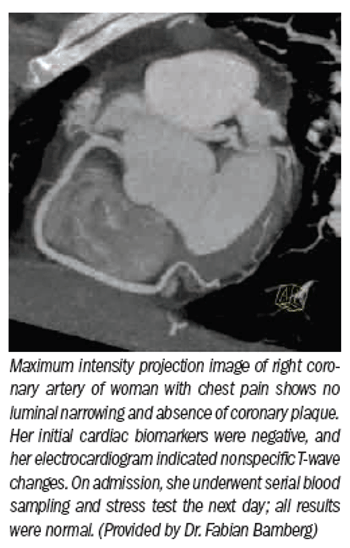

Cardiac imaging researchers are validatingbroader clinical roles for 64-slice and dual-source CT while introducingthe radiological world to evenmore powerful machines that promiseto lower radiation exposure andimprove resolution.